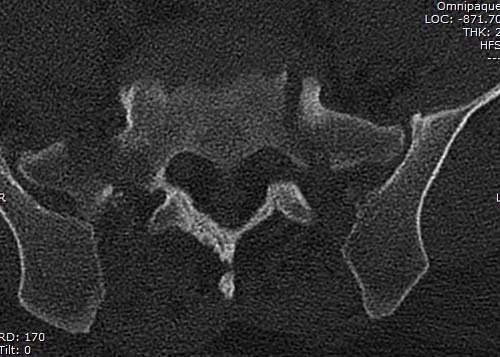

КТ, при детальном рассмотрении виден перелом задних отделов крыла подвздошной кости

KT